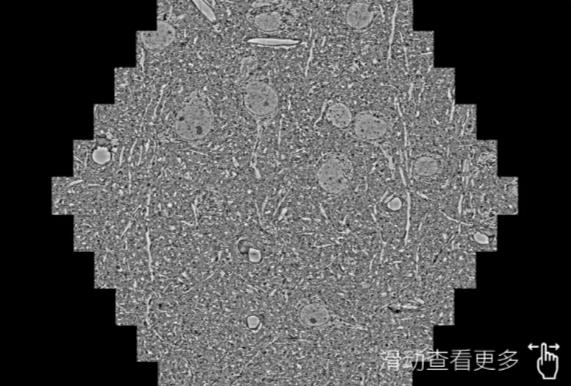

鼠脑切片。左图使用怀化蔡司怀化扫描电镜MultiSEM706对165μmx143pm面积区域成像,耗时仅需1.5秒。右图为鼠脑切片中30μm区域放大效果。样品由芝加哥大学B.Kasthuri提供。